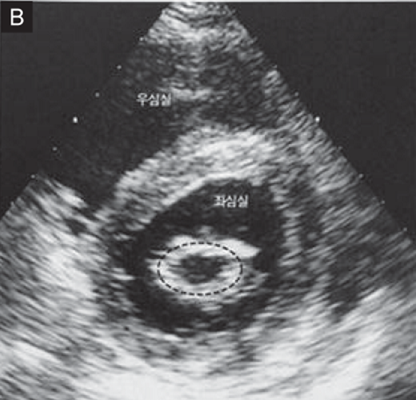

승모판 협착증(Mitral stenosis, MS)